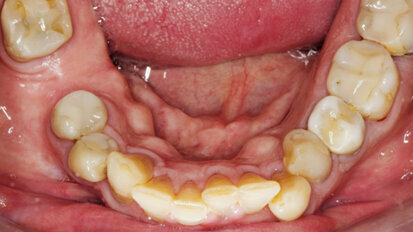

Republika bez kazu